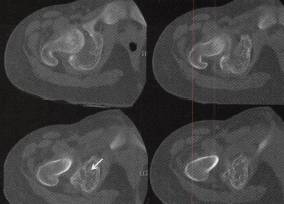

图1右盆骨软骨母细胞瘤

C

D

A.CT平扫见髋臼骨质弥漫性小片状低密度病灶,残存骨小梁,多处骨嵴,外缘关节面侧骨皮质连续性断裂、缺失,内缘骨皮质连续性断裂并伴少许骨膜反应,病灶向关节腔内侵犯较明显,关节腔明显积液;

B〜D.CT骨窗见髋曰弥漫性溶骨性骨质破坏、骨皮质缺失及骨嵴,轻度骨膨胀,病灶边缘未见明显硬化